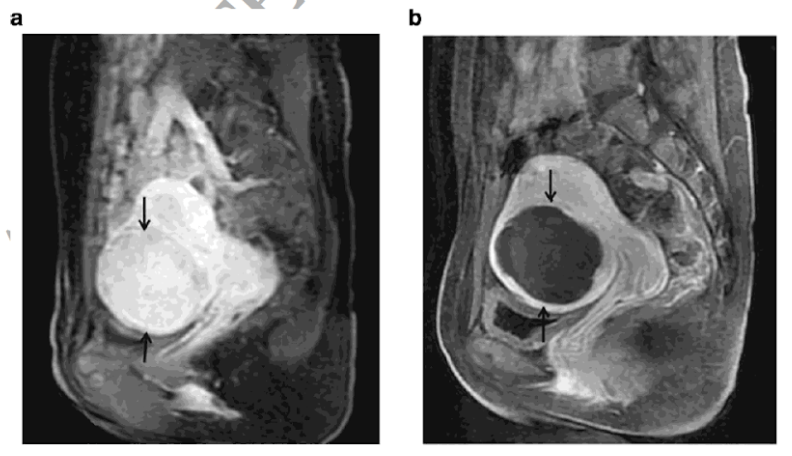

Alterações na RM de contraste (CE-MRI) antes e após ablação.[/caption]Comparação do micro-ondas com a radiofrequência